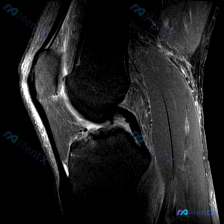

今天整理了一份膝关节MRI读片的病例,挺有代表性,分享下我的分析思路。 影像基本信息 这是一张膝关节矢状位T2加权MRI单层面图像,临床提示观察「软骨异常」。 影像客观所见 先给大家列全所有阳性和阴性发现: 1. 韧带:后交叉韧带、前交叉韧带连续性都好,走行自然,没有断裂、中断,也没有异常高信号 2...